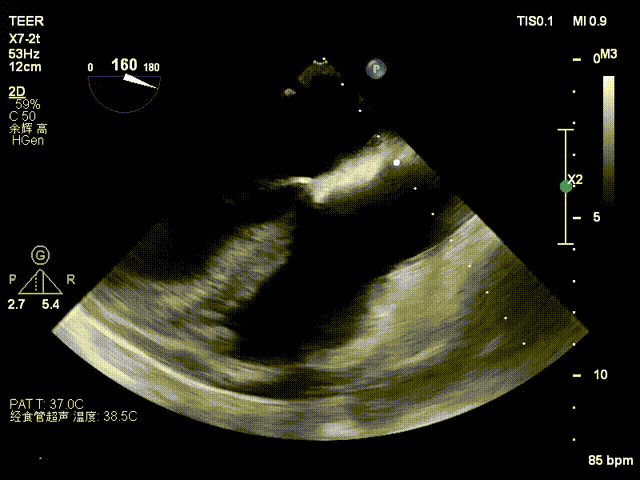

患者为73岁老年男性,经食道超声检查提示:急性二尖瓣腱索断裂合并反流,前叶长度:2.8cm,后叶长度:1.7cm,脱垂宽度:18mm,脱垂高度:8mm,瓣口面积:6.5cm²。

术前影像

左房极小

房间隔增厚